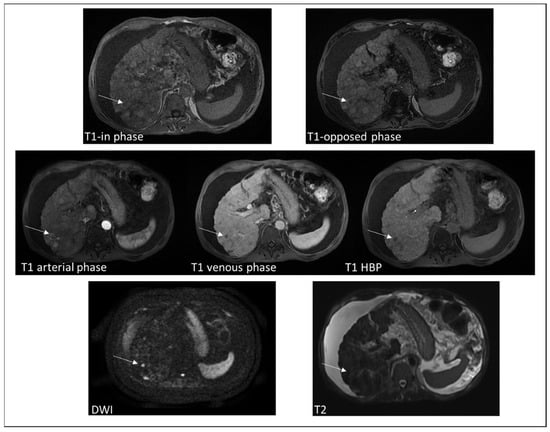

4.2. Extramedullary Hematopoiesis